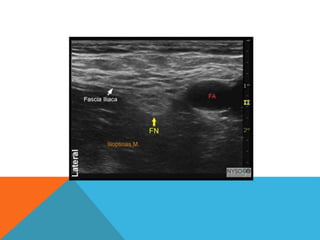

• Identify HYPERECHOIC oval or triangular shaped femoral nerve lateral

to the artery on the iliopsoas muscle, under fascia iliaca

• Femoral nerve triangle created by the femoral artery medially, fascial planes

anteriorly and the iliopsoas muscle posteriorly

Identification of the femoral nerve often is made easier by slightly tilting the

transducer cranially or caudally. This adjustment helps "brighten" up

the nerve and makes it appear distinct from the background

The goal is to place the needle tip immediately adjacent to the lateral

aspect of the femoral nerve, either below the fascia iliaca or between

the two layers of the fascia iliaca, into the wedge-shaped tissue space

lateral to the femoral artery.

Proper deposition of local anaesthetic is confirmed by observation of the

femoral nerve being lifted off of the surface of the iliopsoas muscle or

of the spread of the local anaesthetic above in the wedged-shaped

space lateral to the artery.